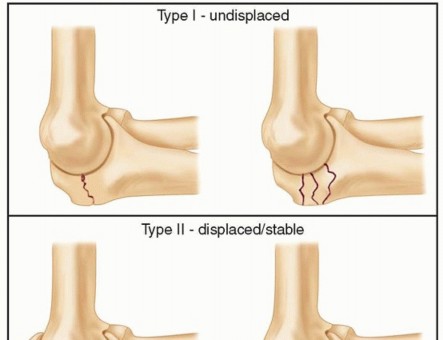

Open Reduction and Internal Fixation of Radial Head and Neck Fractures